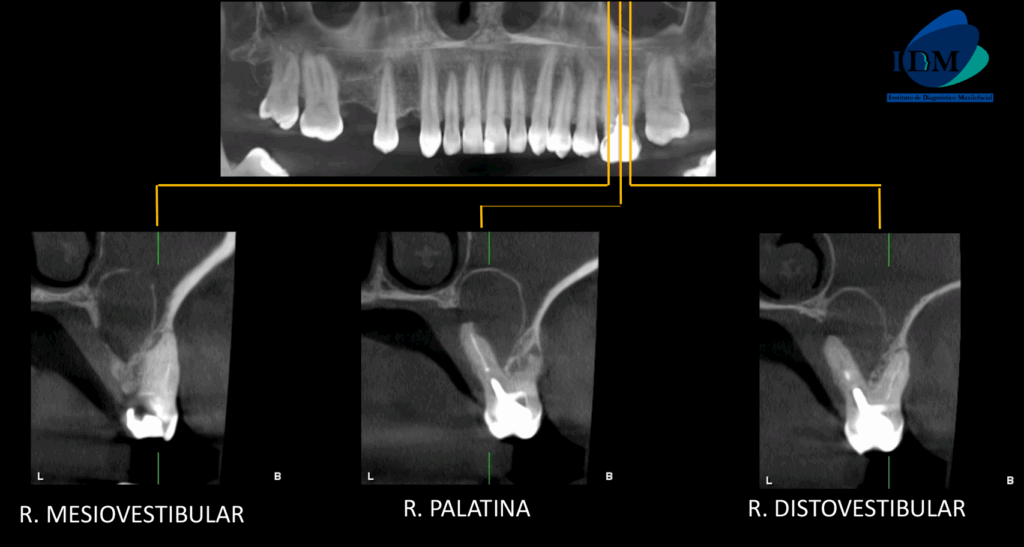

A la evaluación de la tomografía computarizada en cortes axiales, transaxiales y tangenciales se observa la pieza 16 con la raíz mesiovestibular con una obturación parcial y sobre extendida del conducto, asimismo presenta un conducto colateral obliterado y un proceso osteolítico periapical y reabsorción radicular externa del tercio apical; la raíz distovestibular presenta también una obturación parcial de conducto y la raíz palatina presenta un espigo intrarradicular, obturación parcial y subextendida del conducto y una imagen hipodensa corticalizada que desplaza hacia cefálico el piso de seno maxilar y compromete la tabla ósea palatina compatible con quiste radicular, asimismo ocasiona un engrosamiento de la mucosa antral ipsilateral compatible con sinusitis de origen odontogénico.

CORTES TANGENCIALES

CORTES TRANSAXIALES